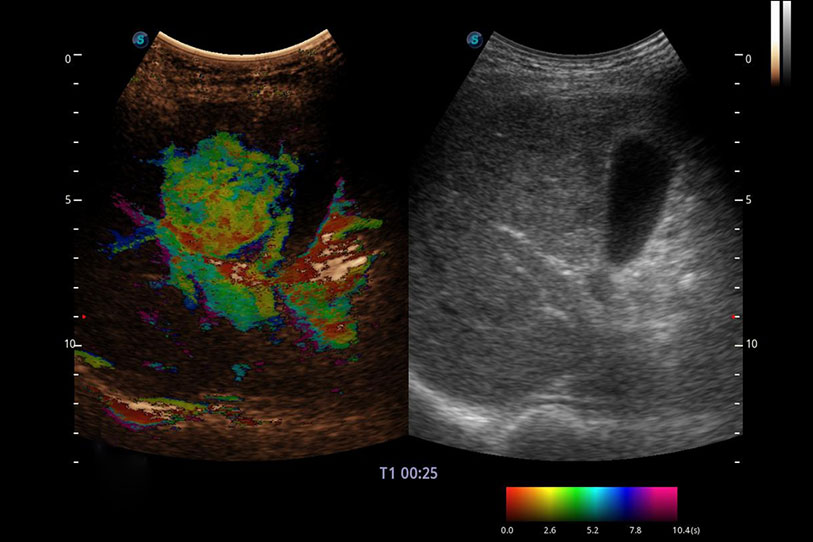

采用红、橙、黄、绿、青、蓝、紫这七种肉眼最为敏感的色彩,直观地显示组织内血流灌注的时间先后信息,更精准捕捉血流灌注走行细节。